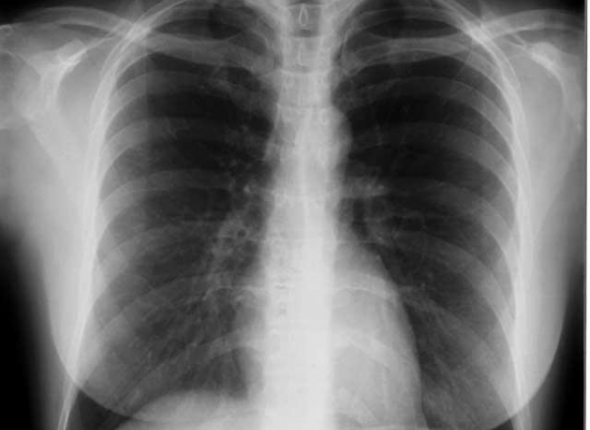

Фото: из открытых источников

Цифровой флюорограф в поликлинике областной больницы в Биробиджане, который используется для оказания первичной специализированной медико-санитарной помощи, изношен на 100% и создает опасность для жизни и здоровья пациентов. К такому выводу пришла прокуратура и обратилась в суд с требованием приобрести новый цифровой аппарат для исследования легких. В итоге управление здравоохранения правительства ЕАО обязали выделить деньги на новый цифровой флюорограф, а областная больница должна совершить столь нужную покупку не позднее 30 декабря 2017 года, сообщила ИА ЕАОMedia старший помощник прокурора области Жанна Крепкогорская.

Как установлено проверкой, в областной поликлинике эксплуатируется цифровой флюорограф для оказания первичной специализированной медико-санитарной помощи, степень износа которого на сегодняшний день составляет 100%. Отсутствие необходимого медицинского оборудования нарушает права граждан на получение качественной и своевременной медицинской помощи, создает опасность их жизни и здоровью.